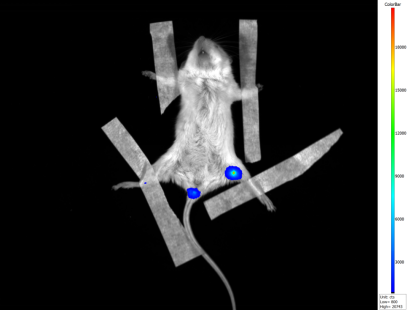

3.肺肿瘤研究领域的应用

4周龄雌性Nod/Scid免疫缺陷小鼠,尾静脉注射A549肺癌细胞,5周后用IVScope 8200系统检测,检测前10min腹腔注射底物荧光素,并注射4%水合氯醛麻醉。

(曝光5min) (曝光5min)